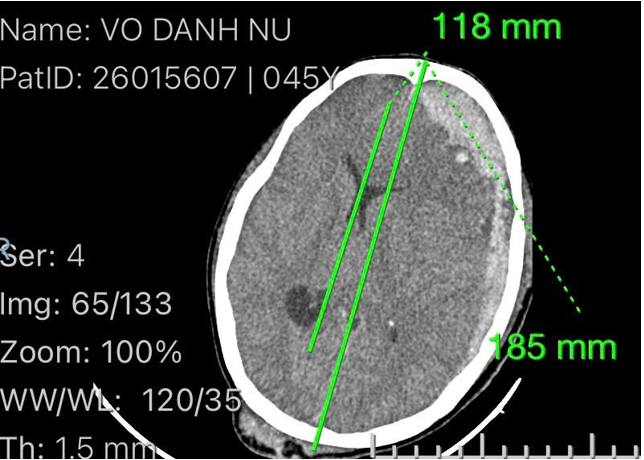

Kết quả CT scan sọ não không cản quang cho thấy nhiều tổn thương nặng như: máu tụ dưới màng cứng bán cầu trái, máu tụ ngoài màng cứng vùng trán trái, dập não xuất huyết trán trái, nứt sọ chẩm phải kèm phù não nhiều và phù não lan toả.

Hình ảnh cận lâm sàng của bệnh nhân trước khi phẫu thuật